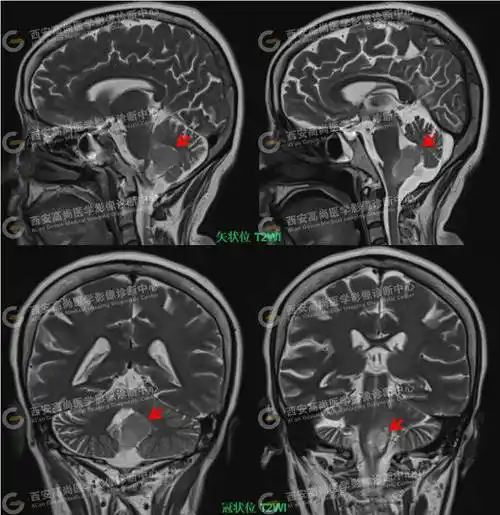

男,52岁,外院ct发现第四脑室高密度占位9年余.